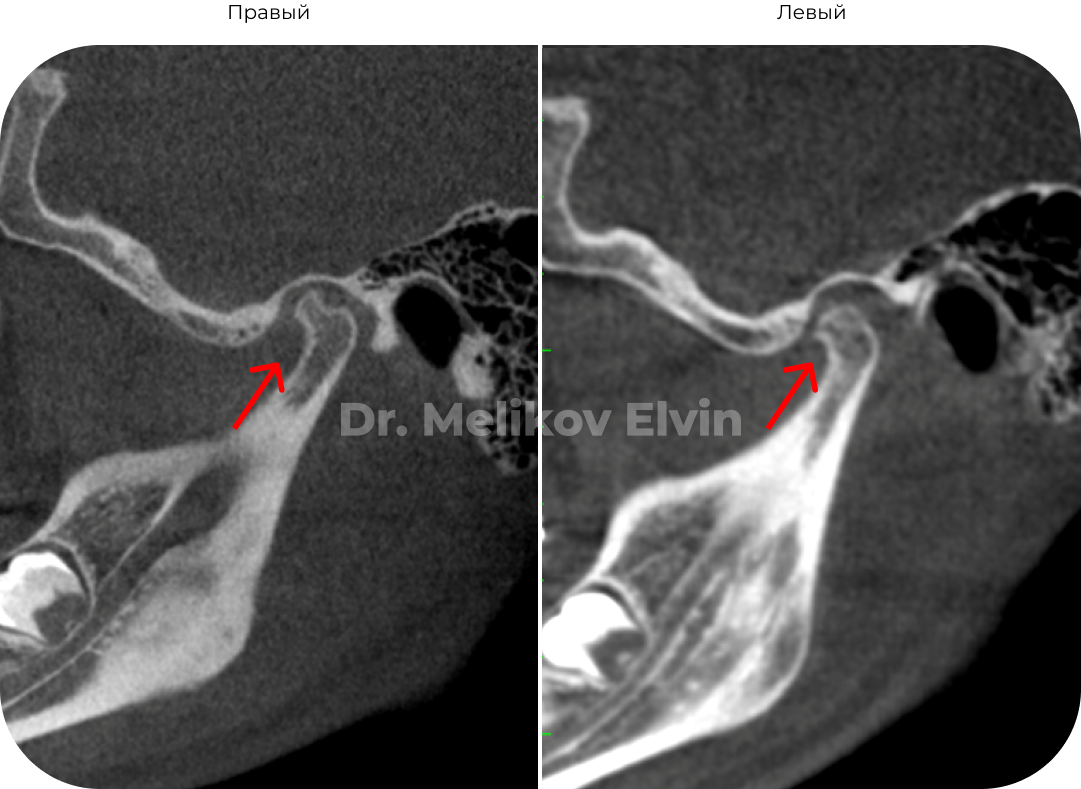

Компьютерная томография ПОСЛЕ.

После реабилитации.

Суставной диск репонировался: позиционирован на головке мыщелкового отростка.

Декомпрессия в суставе, восстановилась трофика и целостность кортикальной пластинки.